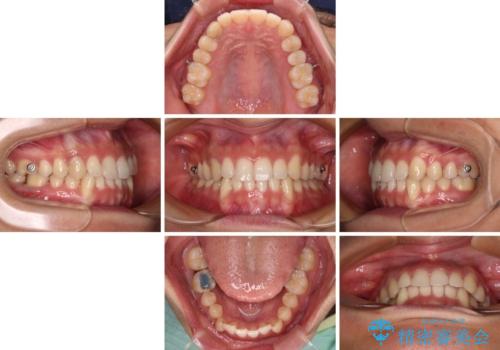

- 下顎の八重歯を気にして来院された患者様です。

マウスピース矯正でもワイヤー矯正でも対応可能であり、マウスピースによる治療を希望されたため、インビザラインを用いることとしました。

下顎前歯にデコボコが集中していたため、顎間ゴムによる後方移動とIPR(歯と歯の間を削ること)により歯列を整えることとしました。

しっかりとマウスピースを装着してくださったおかげで、スムーズに治療を終えることができました。

矯正治療途中で右下奥歯の虫歯治療を近医で行ったようで、既に神経が失活していたと合わせて矯正治療後に補綴治療を行う予定です。